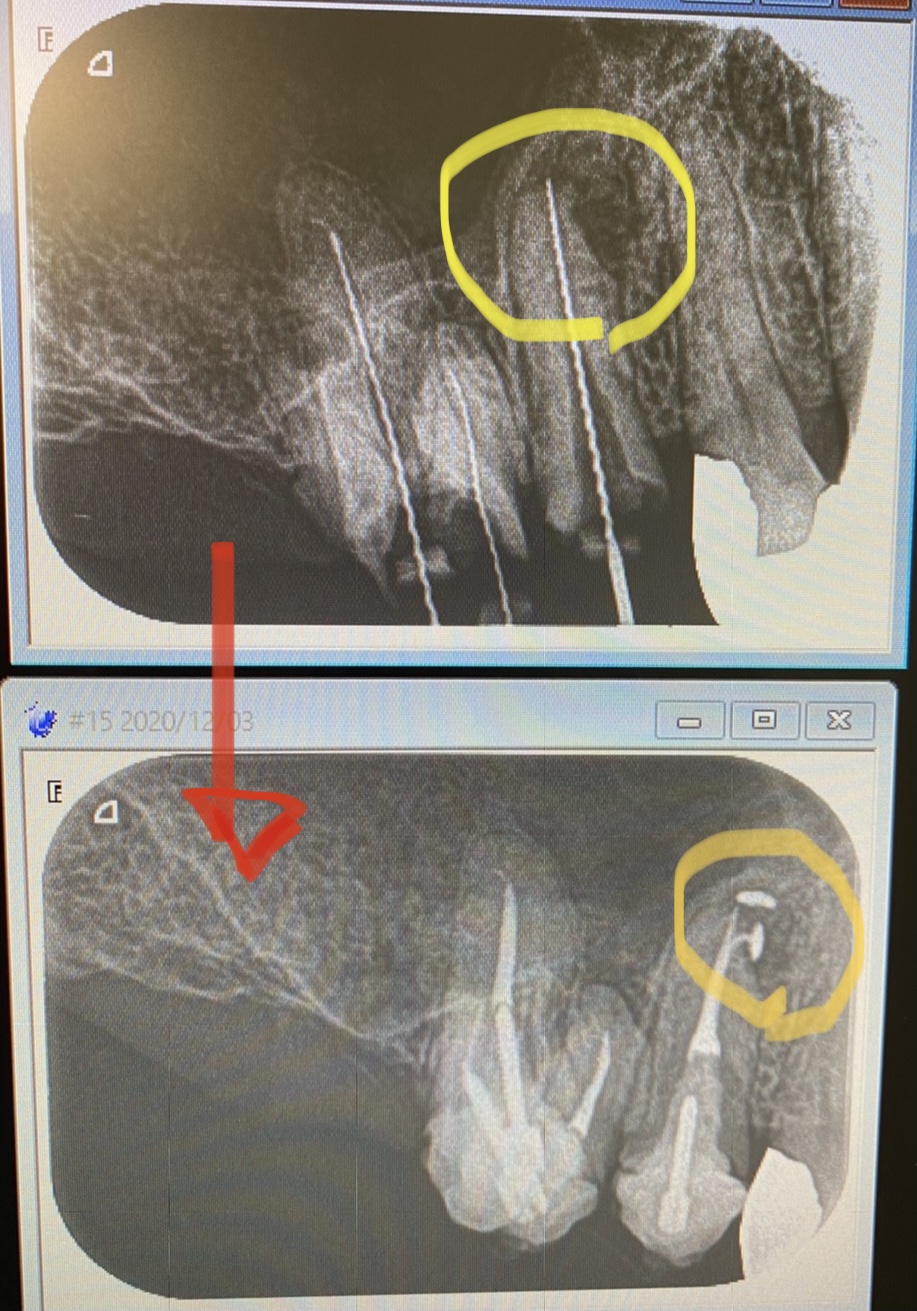

1ヶ月半程、根管の殺菌消毒して本日根管充填(最終的な根管充填材)へ。

根管の尖端付近が枝分れしています

このようにな『側枝』が空洞化していると、根管の感染が再燃する一因になります。

普通の根管充填方法ではストレートの本管しか充填材は入りません💦

このような湾曲した細い枝に充填出来るのは、NT(ニッケルチタンファイル)オブチュレーションシステムを採用しているからです。

後ろの6番は3根ありますが、そのうちの外側2根を切断して、しつこく残す治療を選択。٩( ‘ω’ )و

C Tでも分かりますね